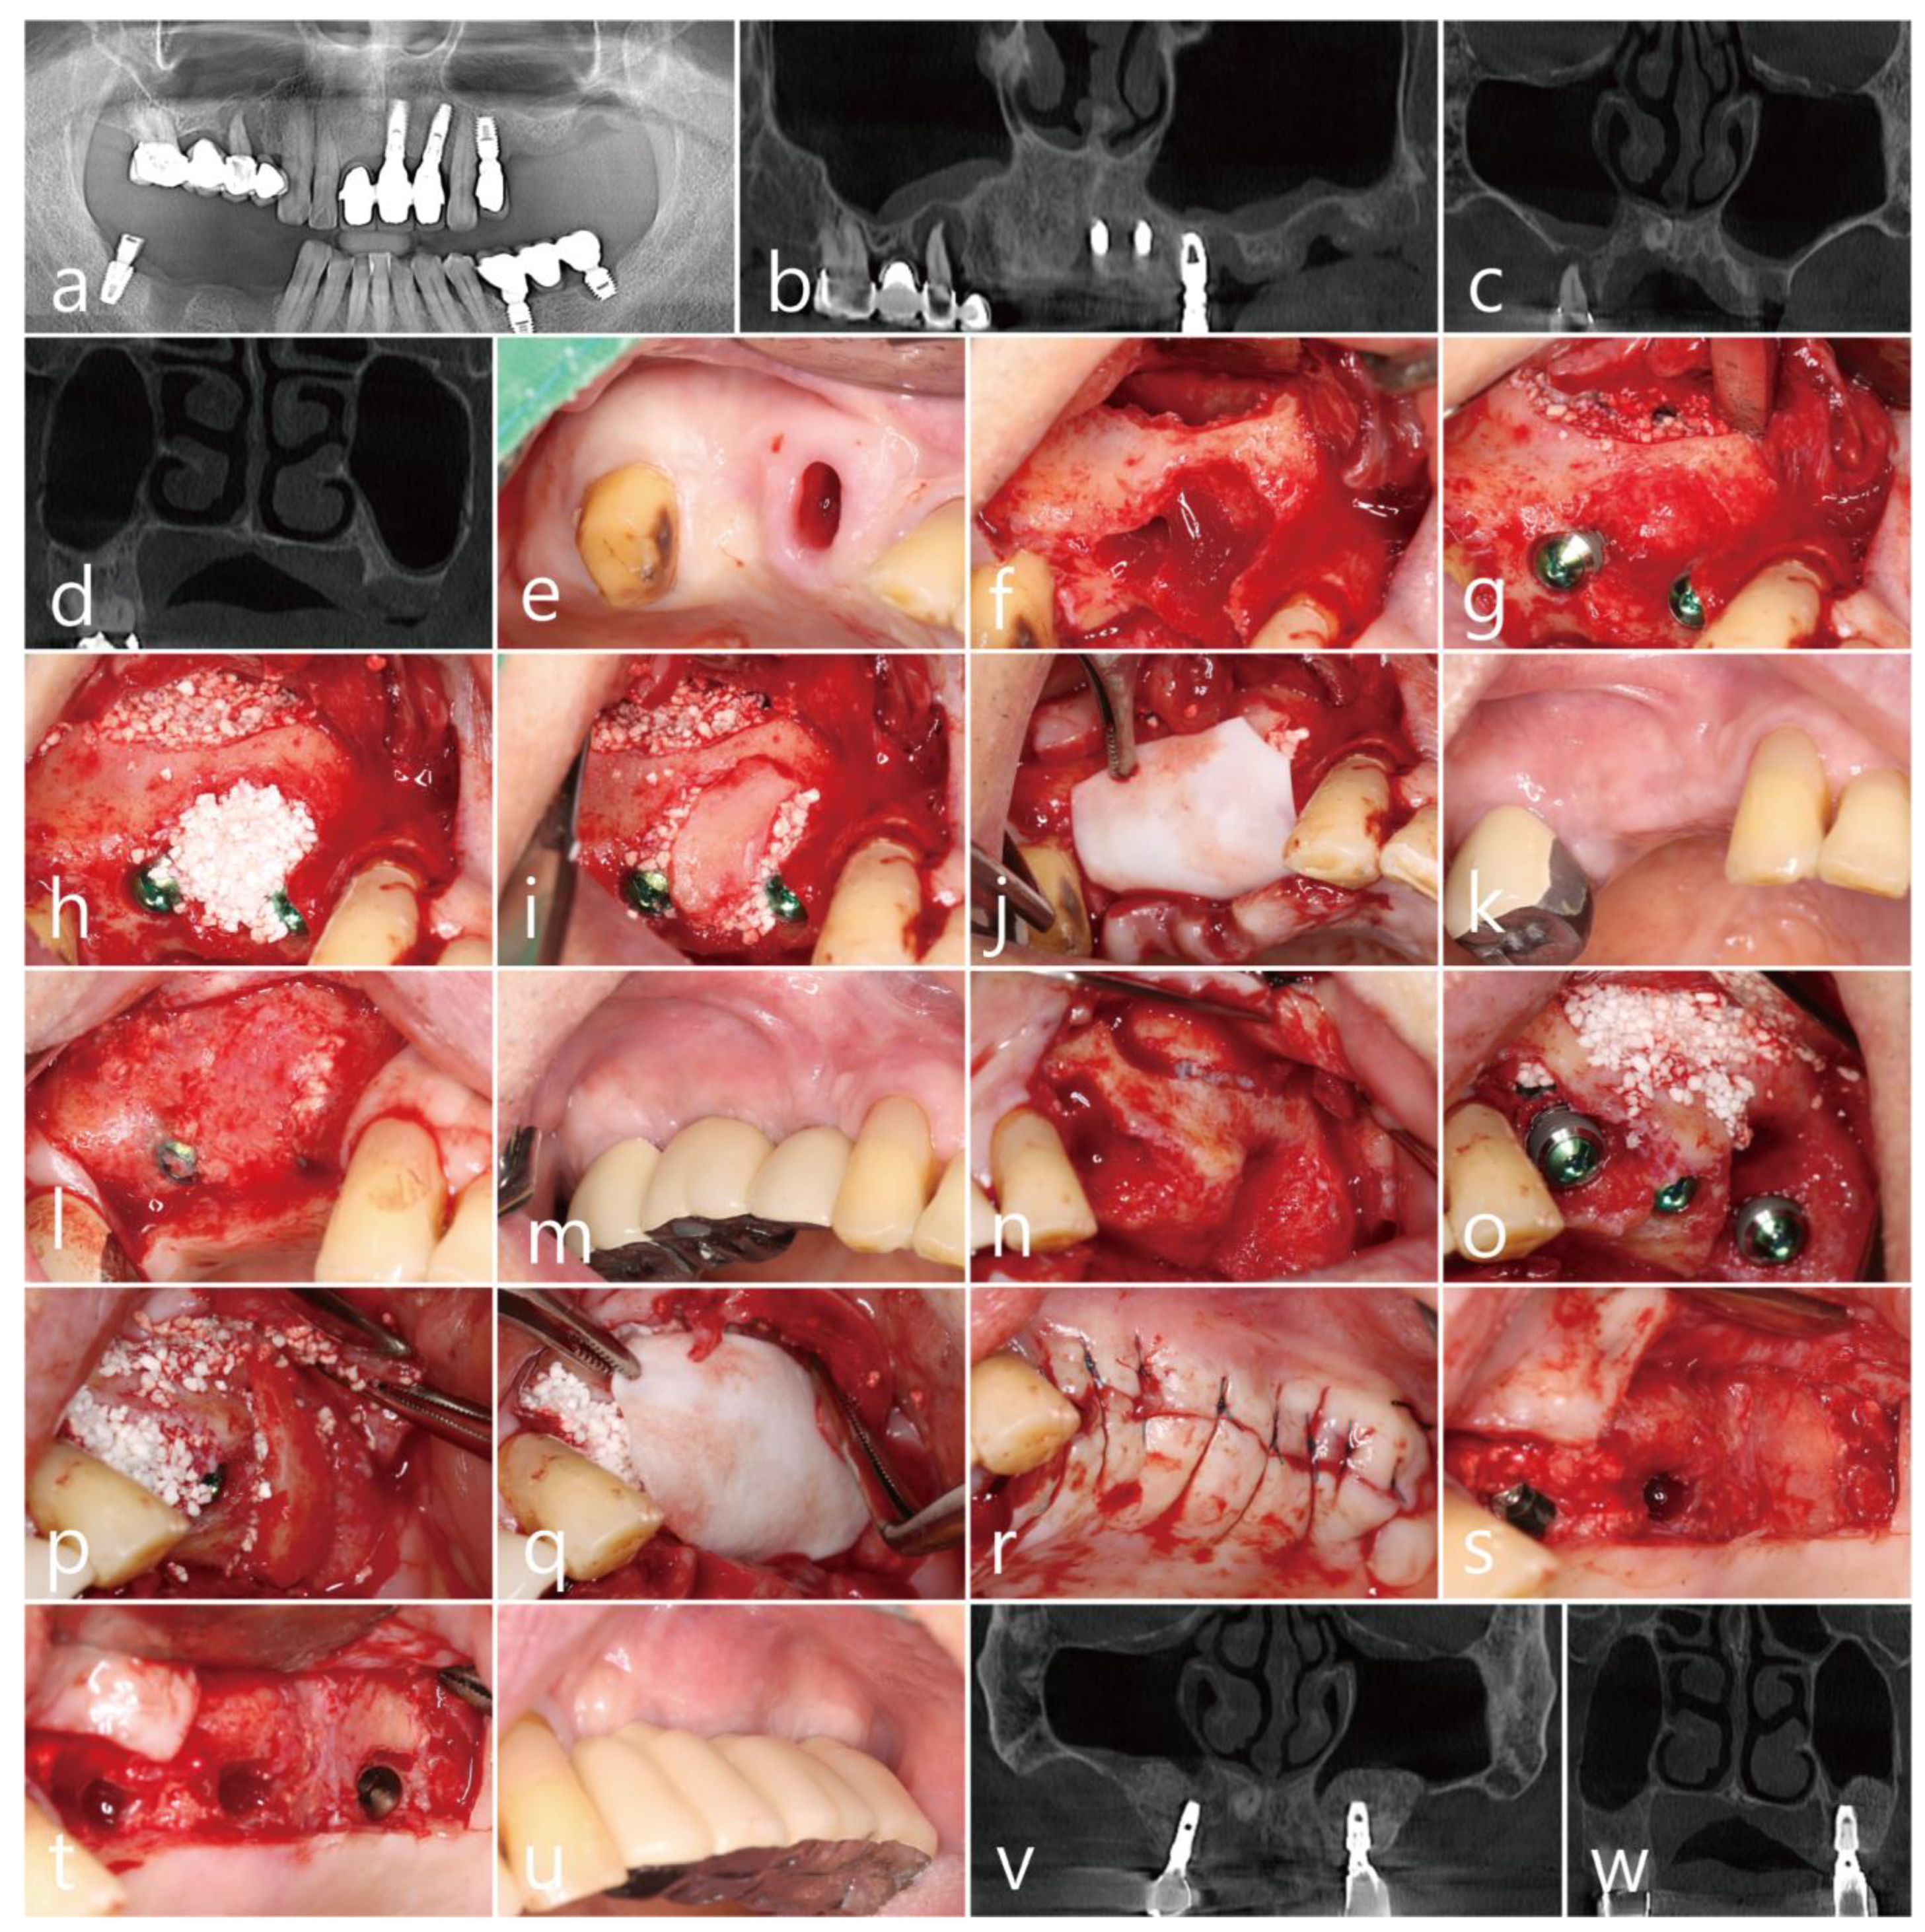

The patient was a 65 years old nonsmoking male, who visited the clinic for the treatment of a failed implant and re-implantation. The patient did not have any systemic diseases that could interfere with the operation, except for hyperlipidemia. A preoperative panoramic radiograph revealed severely resorbed bone around #15 (Figure 3a). On the panoramic image of the CBCT before the surgery, pneumatization of the left maxillary sinus was observed. In addition, severe bone resorption due to the fact of peri-implantitis was observed on the distal aspect of the #24 implant (Figure 3b). On the preoperative coronal CBCT scan, the buccal bone of the #15 tooth was severely resorbed (Figure 3c), and the residual bone height of the left posterior molar site was significantly reduced (Figure 3d). PSAAs were observed on both lateral sinus walls. On the right, the diameter of the PSAA was 1.5 mm, and the vertical position was 7.3 mm from the floor of the right maxillary sinus. On the left, the diameter of the PSAA was 1.3 mm, and the vertical position was 11.2 mm from the floor of the left maxillary sinus (Table 1).

After removal of the old prosthesis, the #15 tooth was extracted under local anesthesia with 2% lidocaine (containing 1:100,000 epinephrine) (Figure 3e). The mucoperiosteal flaps were reflected, followed by a lateral window preparation for MSA. The lateral sinus bony window was obtained, and the sinus membrane detached from the sinus floor without perforation. The severe bone defect around the extraction socket of the #15 tooth was observed (Figure 3f). Sinus bone augmentation was performed using an Osteon III (particle size 0.5–1.0 mm; Genoss Co., Ltd., Suwon, Republic of Korea), and implants (Implantium, Dentium Co., Ltd., Suwon, Republic of Korea) were placed. A mesial bony defect was observed around the implant during the procedure (Figure 3g) and was filled with Osteon III (particle size 0.2–0.5 mm; Genoss Co., Ltd., Suwon, Republic of Korea) (Figure 3h). The obtained lateral sinus bony window was placed on the bony defect without fixation after slight trimming to match the size and shape of the defect (Figure 3i). The surgical site was covered with a resorbable collagen membrane (Genoss Co., Ltd., Suwon, Republic of Korea) (Figure 3j). The mucoperiosteal flaps were closed with 5-0 nylon. The healing was uneventful, and the wound was not exposed (Figure 3k). The uncovering procedure was performed six months after the surgery. The grafted lateral window bone was well integrated with the surrounding bone (Figure 3l). Healing abutments were inserted, and the flaps were closed. After two months, the final prosthesis was delivered (Figure 3m).

On the same day, lateral MSA and implant placement were performed in the left maxillary posterior region. Under local anesthesia with 2% lidocaine (containing 1:100,000 epinephrine), the mucoperiosteal flaps were reflected. The implant placed in the #24 site was explanted, and a lateral sinus window site was prepared for MSA. The extraction socket of the #27 tooth had a wide-deep defect (Figure 3n). The MSA using an Osteon III (particle size 0.5–1.0 mm; Genoss Co., Ltd., Suwon, Republic of Korea) was performed, and three implants were placed (Table 1). A buccal bony defect was observed around the #27 implant site (Figure 3o). After filling the bony defects with Osteon III (particle size 0.2–0.5 mm; Genoss Co., Ltd., Suwon, Republic of Korea), the obtained lateral sinus bony window was positioned in the #27 implant site (Figure 3p). The surgical site was covered with a resorbable collagen membrane (Genoss Co., Ltd., Suwon, Republic of Korea) (Figure 3q), and the flaps were closed with 5-0 nylon (Figure 3r). Antibiotics (ciprofloxacin; 500 mg; Ildong Pharmaceutical Co., Ltd., Seoul, Republic of Korea) and a nonsteroidal anti-inflammatory drug (Etodol; 200 mg; Yuhan Co., Ltd., Seoul, Republic of Korea) were prescribed for two weeks. The healing was uneventful. The uncovering procedure was performed six months after the surgery. The buccal bony defects around the #27 implant were resolved, and the transplanted lateral sinus window was well integrated with the surrounding native bone (Figure 3s). The bone above the cover screw was removed using a round surgical bur (Figure 3t). The prosthesis was delivered after two months (Figure 3u).

The sinus augmented bone obtained from the MSA was well integrated on the coronal images of the CBCT performed six months after the final prosthesis was delivered (Figure 3v,w).

Figure 3. Case 3: (a) preoperative panoramic radiograph; (b) preoperative panoramic image of the CBCT scan; (c) posterior superior alveolar arteries (PSAAs) are shown on the coronal images of the preoperative CBCT scans on both sides; (d) coronal image of the preoperative CBCT scan showing a severely resorbed bone defect around the extraction site of the left maxillary second molar; (e) preoperative clinical view after extraction of the right maxillary second premolar; (f) after flap reflection, a lateral bony window was prepared for maxillary sinus augmentation; (g) a bony defect was observed after implant placement and sinus augmentation; (h) the buccal bony defect was filled with particulate bone graft; (i) the obtained lateral bony window was placed on the bony defect without fixation; (j) the surgical site was covered with a resorbable collagen membrane; (k) clinical view six months after surgery; (l) the lateral bony window was well incorporated with the surrounding native bone at six months after surgery; (m) clinical view after final prosthesis delivery; (n) after flap reflection, the #24 implant was explanted and a lateral bony window was prepared for maxillary sinus augmentation; (o) after sinus augmentation and implant placement, the buccal bony defects are shown; (p) after filling the buccal bony defect with particulate bone graft, the obtained lateral bony window was positioned on the bony defect; (q) the surgical site was covered with a resorbable collagen membrane; (r) the flaps were closed with minimal tension; (s) the uncovering procedure was performed six months after surgery, and the grafted lateral bony window was well integrated with the surrounding native bone; (t) the bone above the cover screw was removed with a round surgical bur, and after the healing abutments were inserted, the flaps were closed; (u) clinical view after final prosthesis delivery; (v) coronal CBCT image at six months after prosthesis delivery; (w) coronal CBCT scan showing the filling of the defect around the implant placed at the extraction site of the left maxillary second molar.